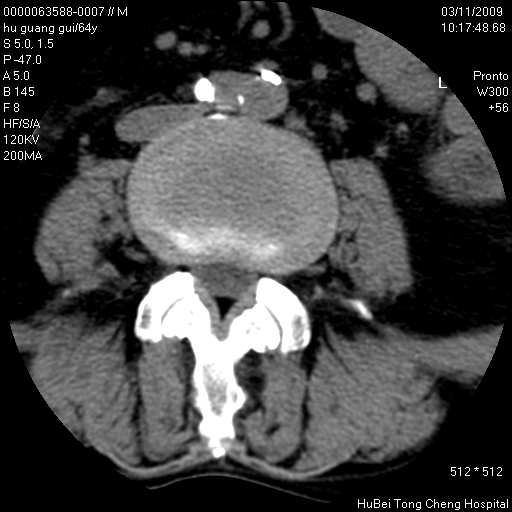

患者 男,64岁。腰痛十余天。(临床未提供其他病史)

临床诊断:腰痛原因待查(腰椎间盘突出症?)。

腰椎间盘ct轴位平扫(层厚5mm,层距4mm),图像如下:

腰椎退行性变,腰4—5椎间盘膨出。

1.腰椎退行性变,腰4—5椎间盘膨出。

1)腰椎退行性变,l4—5椎间盘膨出。2)骶骨右侧块骨转移瘤可能,3)水平骶椎。建议作一步检查。